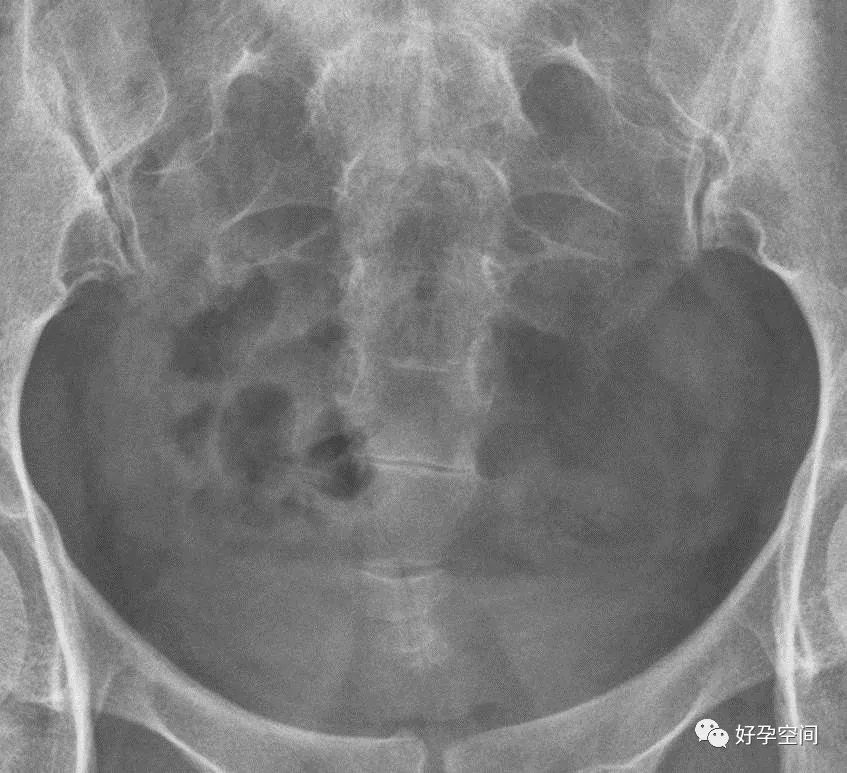

盆腔平片